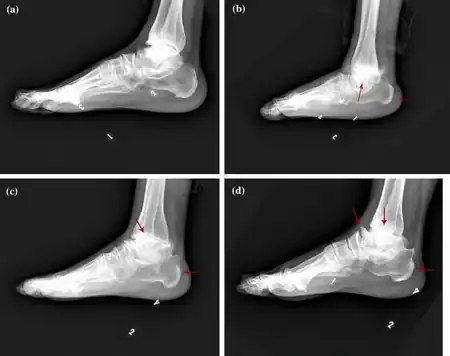

| a-d) Characteristics of child and adult Kashin-Beck disease individuals | |

Kashin–Beck disease (KBD) is a chronic, endemic type of osteochondropathy (disease of the bone) that is mainly distributed from northeastern to southwestern China, including 15 provinces.[1] Tibet currently has the highest incidence rate of KBD in China.[1] Southeast Siberia and North Korea are other affected areas.[1] KBD usually involves children ages 5–15. To date, more than a million individuals have suffered from KBD.[2] The symptoms of KBD include joint pain, morning stiffness in the joints, disturbances of flexion and extension in the elbows, enlarged inter-phalangeal joints, and limited motion in many joints of the body.[3] Death of cartilage cells in the growth plate and articular surface is the basic pathologic feature; this can result in growth retardation and secondary osteoarthrosis.[1] Histological diagnosis of KBD is particularly difficult; clinical and radiological examinations have proved to be the best means for identifying KBD.[4] Little is known about the early stages of KBD before the visible appearance of the disease becomes evident in the destruction of the joints.[4]

In terms of the diagnosis of the condition, it is done via radiographical studies (x-ray)[7]